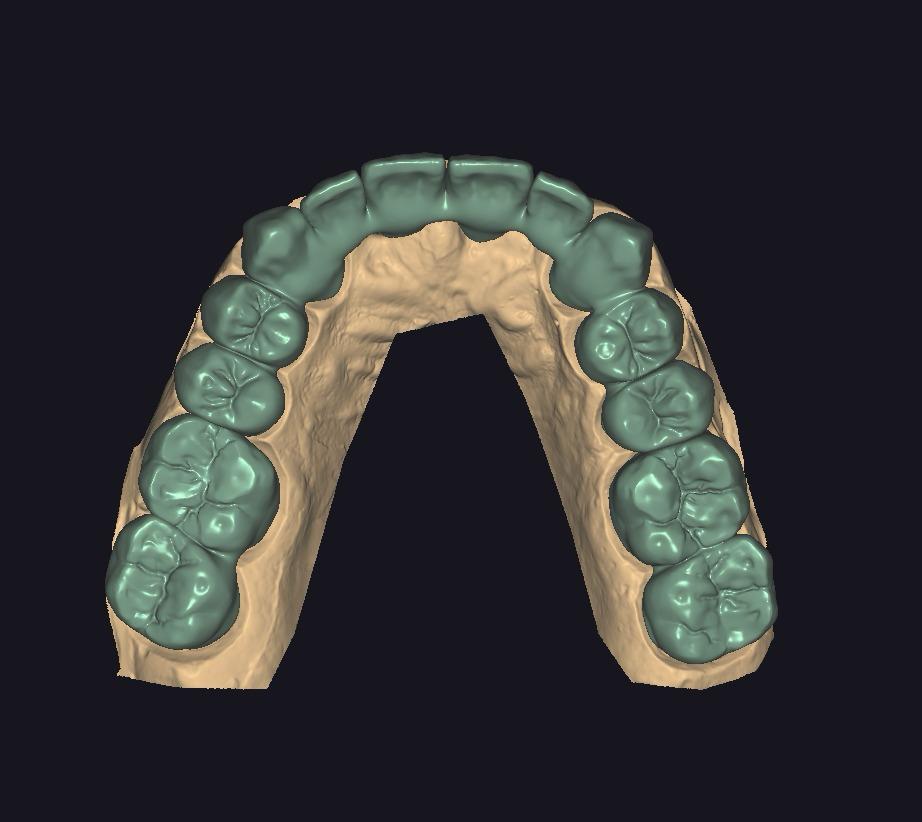

ZIRKONYUM

ZIRKONYUM ALT YAPI

MONOLITIK ZiRKONYUM INLEY ONLEY

MULTILAYER ZiRKONYUM INLEY ONLEY

ZIRKONYUM INLEY ONLEY & LAMINATE